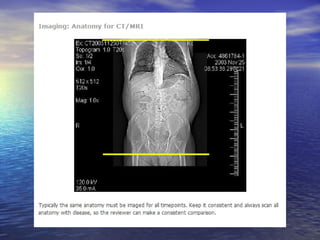

Recist